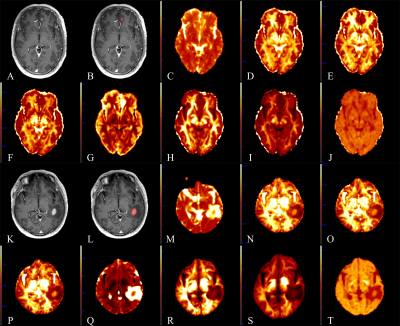

Fig. 1 A 60-year-old male with primary central nervous system lymphoma (PCNSL) in the left frontal lobe (A-J) and a 48-year-old male with atypical high-grade glioma (HGG) in the left temporal lobe (K-T). (A, K): CE-T1 MPRAGE images. (B, L): Region of interest (ROI) (contrast-enhanced area) in the CE-T1 MPRAGE images. (C, M): Parametric maps of MSD. (D, N): NG. (E, O): NGAx. (F, P): NGRad. (G, Q): QIV. (H, R): RTAP. (I, S): RTOP. (J, T): RTPP.

This prospective study was approved by the review board of our hospital and written informed consent was obtained from all patients. We recruited patients with atypical HGG or PCNSL from September 2018 to October 2022. The criteria were as follows: (1) patients who were pathologically diagnosed with HGG or PCNSL; (2) no history of biopsy or antitumor treatment such as chemotherapy, radiotherapy, or surgery before scanning. The exclusive criteria were as follows: (1) HGG with obvious necrosis; (2) images with severe motion or susceptibility artifact; (3) the surgery or biopsy was performed within two weeks after the MRI examination. Finally, 30 patients with atypical HGG and 25 patients with PCNSL were recruited. All patients were examined on a 3T scanner (MAGNETOM Prisma, Siemens Healthcare, Erlangen, Germany) with an integrated 64-channel head and neck coil. The sequences included axial T1WI (time of repetition [TR]=250 ms, time of echo [TE]=2.46 ms, acquisition time=37 seconds), axial T2WI (TR=4090 ms, TE=99 ms, acquisition time=34 seconds), axial T2-tirm dark-fluid (TR=8000 ms, TE=81 ms, acquisition time=1min 38 seconds), axial multi-b-value DWI (TR=2500.0 ms, TE=71 ms, acquisition time=6min 34 seconds) and 3-dimensional (3D) contrast-enhanced T1 magnetization prepared rapid gradient echo (CE-T1 MPRAGE) (TR=2300 ms, TE=2.32 ms, acquisition time=5min 21 seconds). The multi-b-value DWI were acquired using 5 b-values (500, 1000, 1500, 2000, and 2500 s/mm2) distributed in 30 directions and one DWI with b = 0. The MPRAGE sequence was conducted after administering 0.2 mol/kg body weight of gadopentetate dimeglumine (Magnevist, Bayer Schering Pharma AG, Berlin, Germany). After examination, all images of the 3D CE-T1 MPRAGE were reconstructed into 20 slices in the axial planes. The parametric maps of MAP, including return to the origin probability (RTOP), return to the axis probability (RTAP), return to the plane probability (RTPP),non-Gaussianity (NG), axial non-Gaussianity (NGAx), radial non-Gaussianity (NGRad), mean square displacement (MSD) and q-space inverse variance (QIV), were computed from the multi-b-value DWI data using an in-house-developed post-processing software, named NeuDiLab, based on Diffusion Imaging In Python (DIPY; http://nipy.org/dipy). After processing, all parametric maps of MAP were registered to the axial CE-T1 MPRAGE images and the region of interest (ROI) containing the contrast-enhanced area of the tumor (Fig. 1), was manually delineated on the axial CE-T1 MPRAGE images by the consensus of two radiologists (respectively with 10 years and 15 years of experience). Then the average values of RTOP, RTAP, RTPP, NG, NGax, NGrad, MSD and QIV were calculated from the ROI. The three steps above were all performed with the ITK-SNAP (http://www.itksnap.org) software. Statistical analysis was performed using SPSS 21.0 (SPSS Inc., Chicago, IL, USA). Between the atypical HGG and PCNSL groups, the average values of RTOP, RTAP, RTPP, NG, NGAx, NGRad, MSD and QIV were compared using the Mann–Whitney U test between the two groups. Receiver operating characteristic (ROC) curves were constructed to assess the diagnostic performance of significant parameters. Statistical significance was set at P < 0.05.